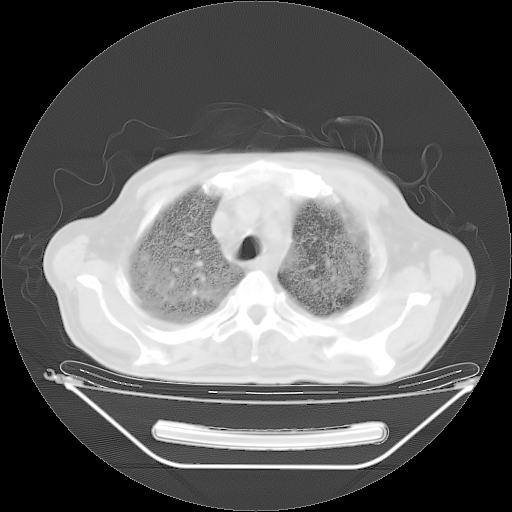

胸腹部CT,诊断意见:左上肺叶钙化灶、左侧胸膜局限性增厚并钙化、胆囊炎。描述部分肺组织呈磨玻璃样改变。